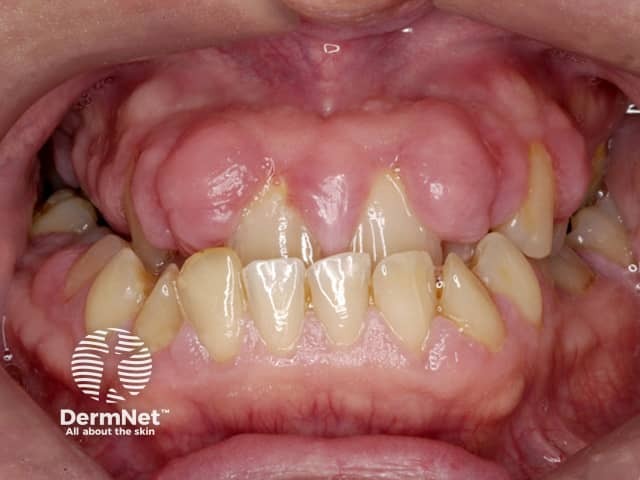

Gum hypertrophy due to ciclosporin